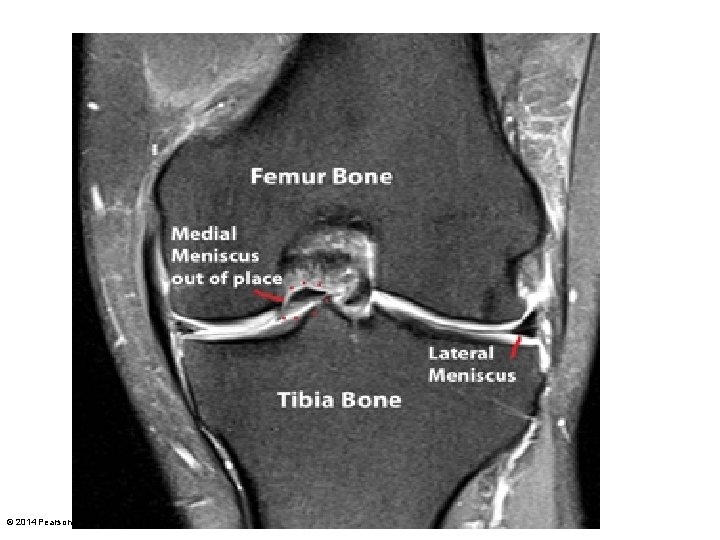

Figure 8. 8 b The knee joint. Anterior cruciate ligament Articular cartilage on medial tibial condyle Medial meniscus Posterior cruciate ligament Anterior Articular cartilage on lateral tibial condyle Lateral meniscus Superior view of the right tibia in the knee joint, showing the menisci and cruciate ligaments © 2014 Pearson Education, Inc.